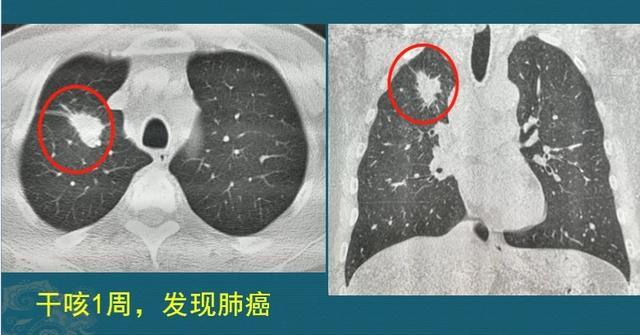

这是一位成年男子,干咳一周发现右侧肺癌,2.2厘米,支气管镜淋巴结穿刺以及痰液检查,明确为浸润性肺腺癌,伴有多发转移。

已经无法做根治性手术,选择放弃治疗听天由命,结果仅仅过了8个月,复查CT显示肿瘤增大到接近8厘米,速度非常快: